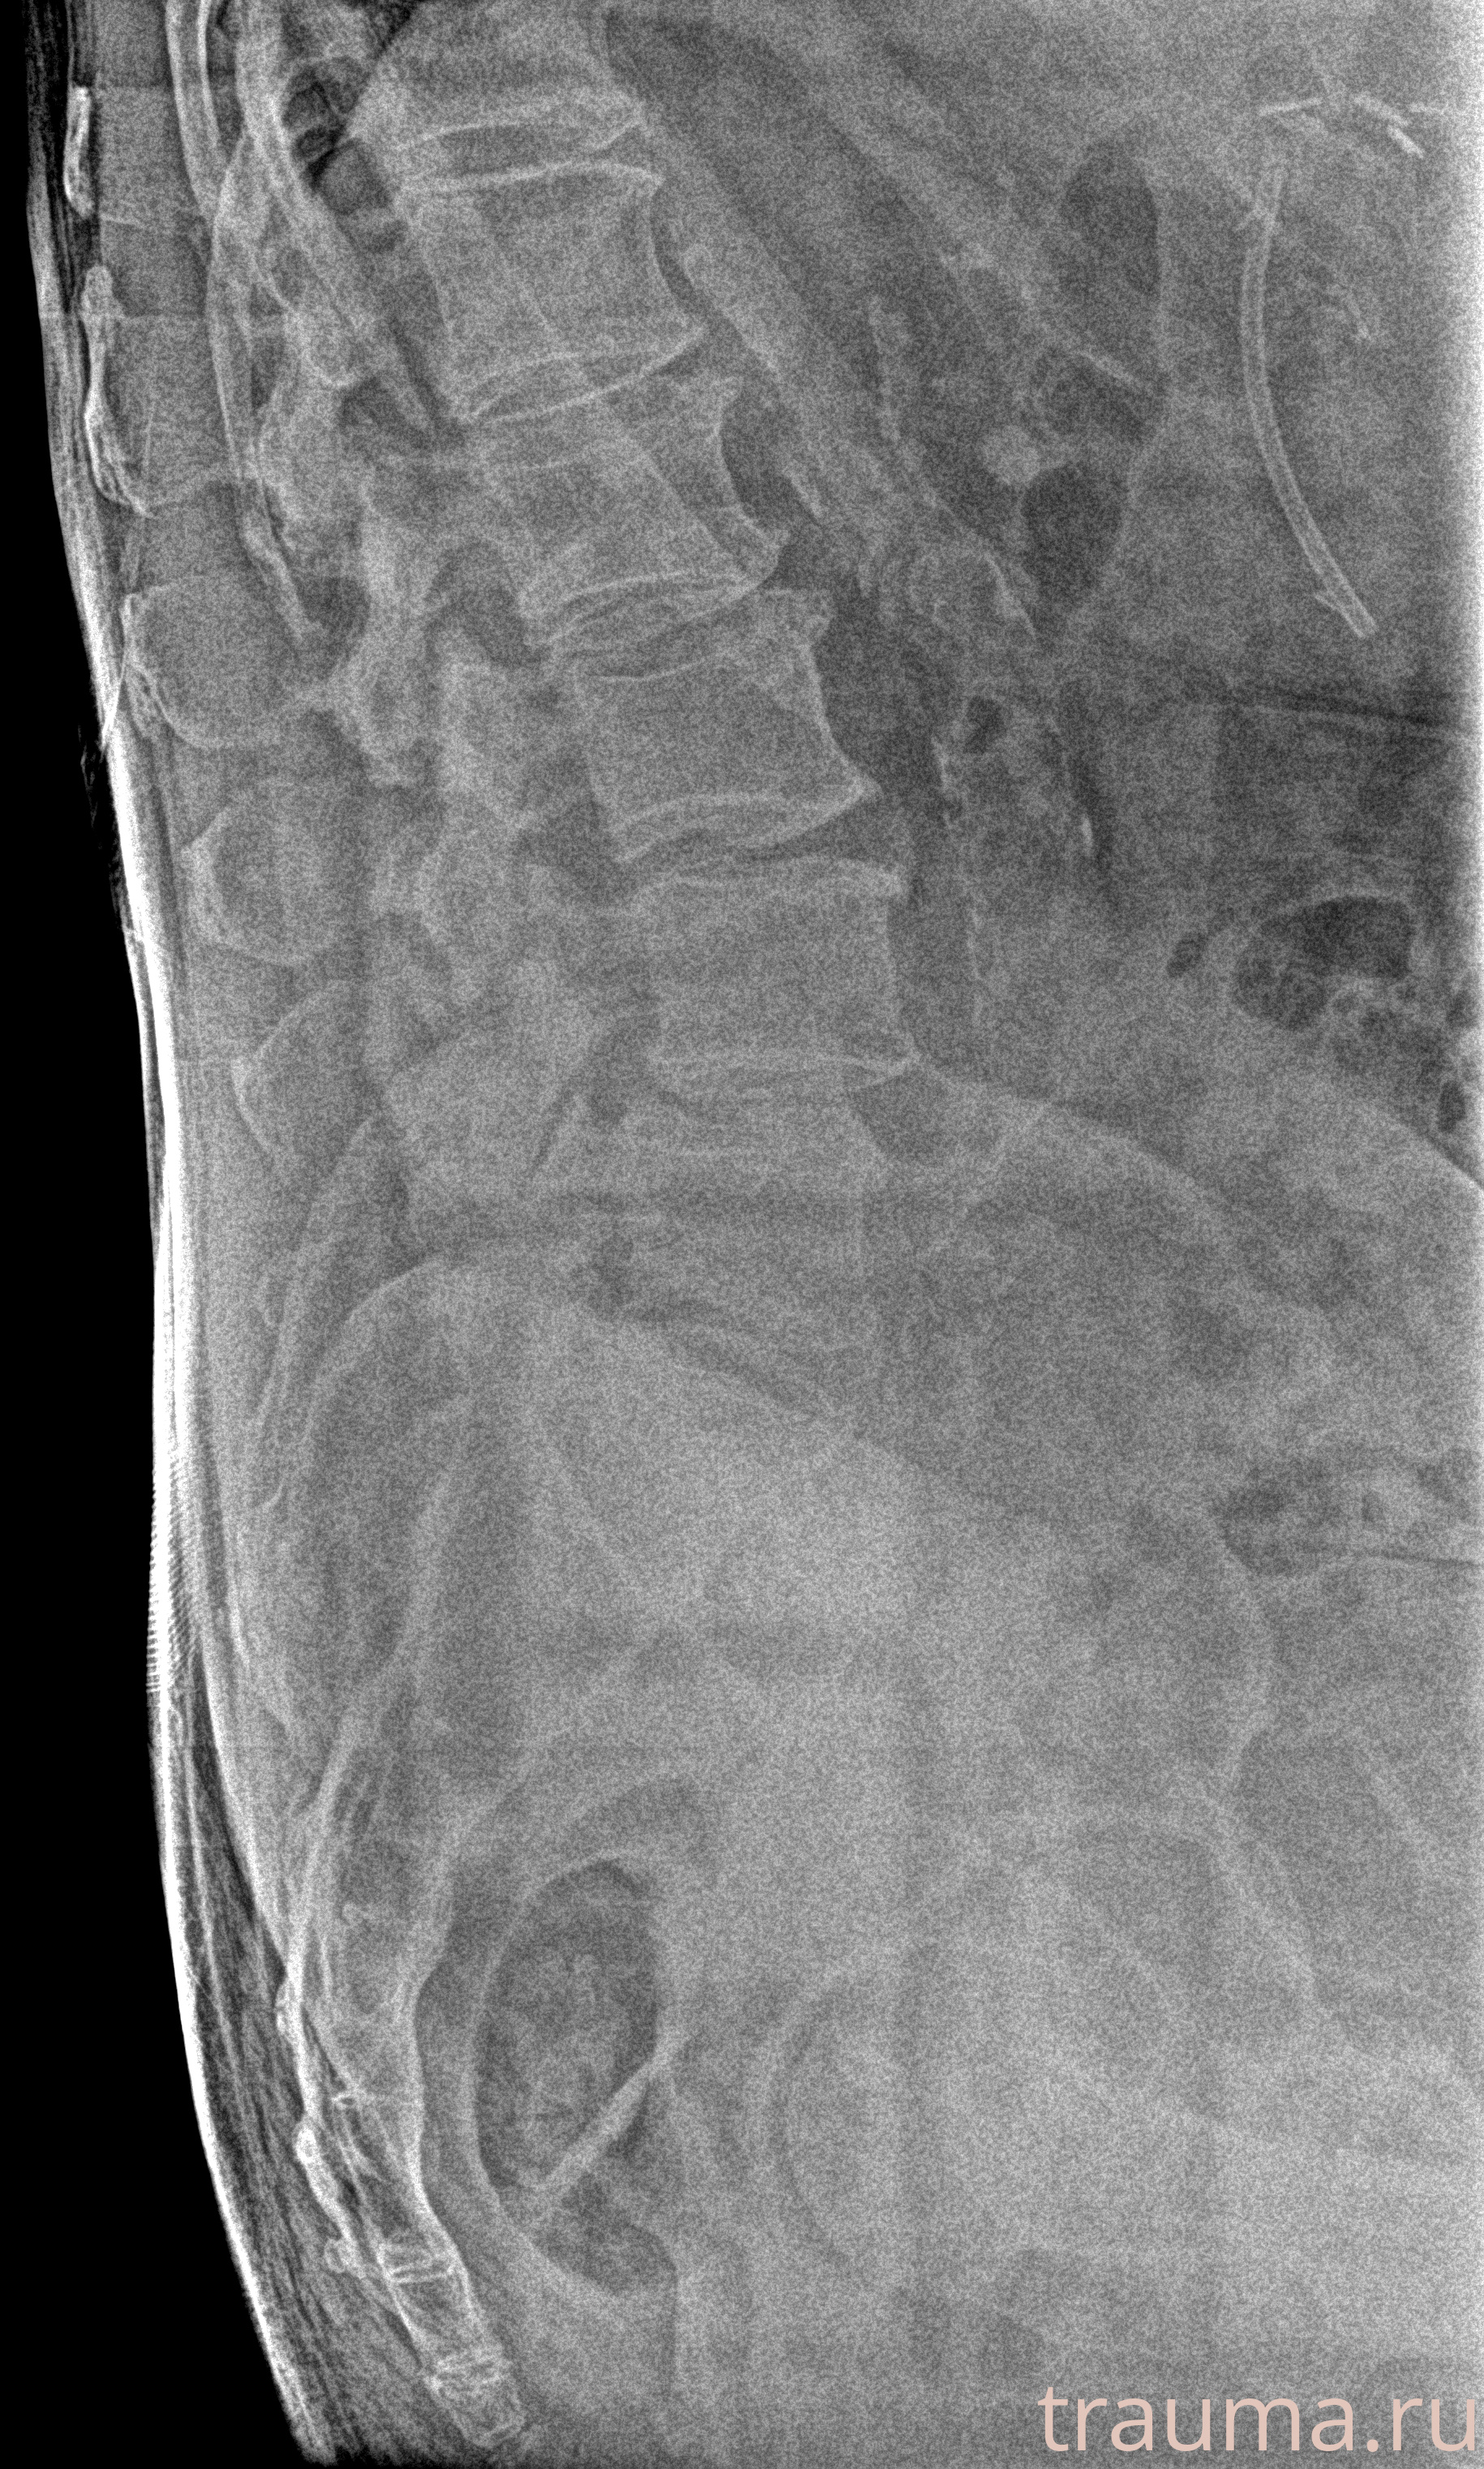

Рентген на дому: по вашему адресу приезжает врач-рентгенолог, травматолог-ортопед с мобильным рентгеновским аппаратом, проводит диагностику травмы или заболевания, делает необходимые рентгенограммы, дает рекомендации по дальнейшему лечению. Получить качественные снимки в домашних условиях возможно благодаря уникальной методике, разработанной МосРентген Центром для института  Склифосовского